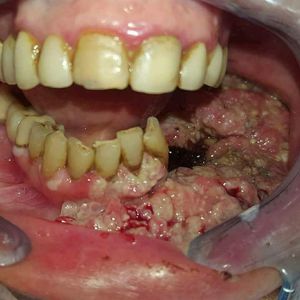

Cancer of Oral Cavity